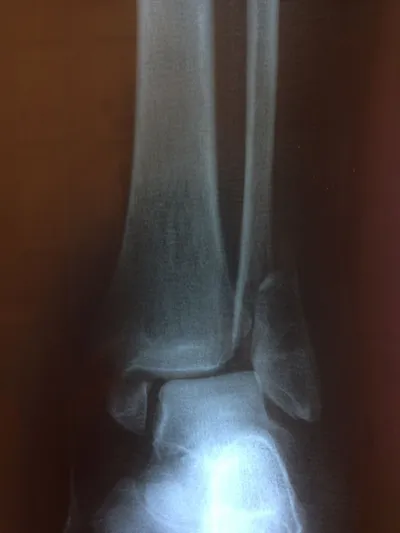

Both the lateral and medial malleolus with fractures with the lateral malleolar fracture classified as a Weber B (at the level of the ankle joint) and the medial malleolar fracture almost transverse (Left x-ray). This is indicative of a Supination External Rotation (SER IV) injury. The fractures are repaired using open reduction with internal fixation (ORIF) technique and fixated with screws and a surgical fractue plate located at the fibular (Right x-ray).

A bimalleolar fracture is a fracture of the ankle that involves the lateral malleolus and the medial malleolus. Studies have shown that bimalleolar fractures are more common in women, people over 60 years of age, and patients with existing comorbidities. Surgical treatment will often be required, usually an Open Reduction Internal Fixation (ORIF). This involves the surgical reduction or realignment of the fracture followed by the implementation of hardware to aid in the healing of the fracture. Usually a plate and screws will be used on the fibular fracture and screws, screws and pins, pins or tension band will most commonly be used on the medial malleolus fracture. A bimalleolar "equivalent" fracture is a fracture of the fibula with rupture of the superficial and deep portion of the deltoid ligaments leaving the medial malleolus intact. Surgical management is common due to the instability of the fracture and displacement of the talus laterally.

The x-ray images below demonstrate another case of a bimalleolar ankle fracture in both and oblique view (left) and anterior - posterior view (right).